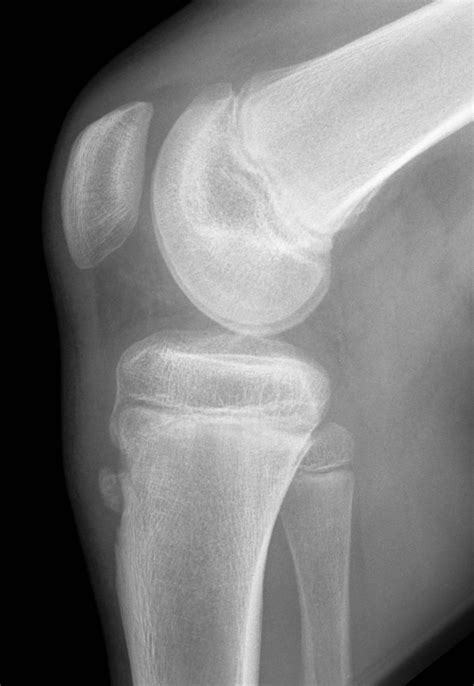

Diagnosing Osgood-Schlatter disease typically involves a physical examination and a review of the patient's medical history. The healthcare provider will ask about the symptoms, the onset of pain, and any recent changes in physical activity. They will also perform a physical examination to assess the affected knee, checking for tenderness, swelling, and any visible bumps.

In some cases, imaging tests such as X-rays, ultrasound, or MRI may be ordered to rule out other conditions and confirm the diagnosis. These tests can help visualize the tibial tuberosity and the patellar tendon, providing a clearer picture of the inflammation and any underlying issues.